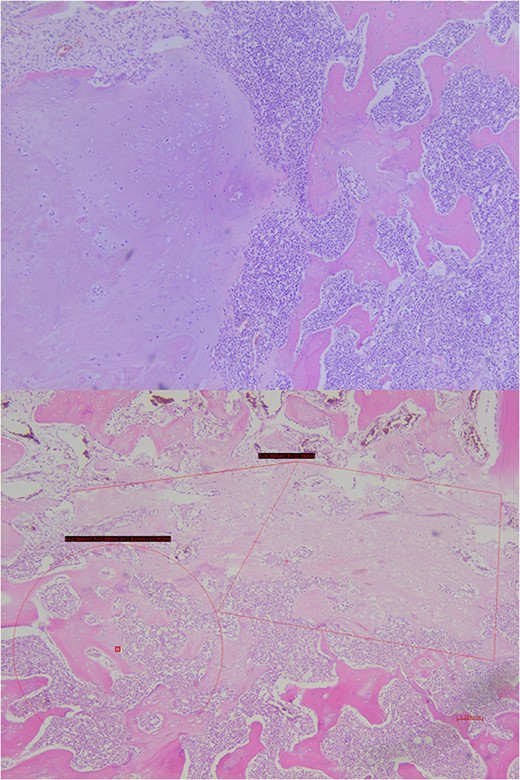

Analysis of the surgical piece established diagnosis of well-differentiated chondrosarcoma (G1) confined to T7 without extension to T6, T8, or soft tissues. Surprisingly, infiltration of high-grade neoplastic component of hematolymphoid type was present. Immunohistochemistry was consistent with DLBCL germinal center subtype (vimentin+/CD45+/CD20+/CD10+/BCL-6+/Ki67 > 80%) (Figs 6–8).

Histopathological exam, macroscopic study. A lobulated lesion (3.8 × 2.6 × 2.9 cm) involves 80% of the central vertebra (T7) and presents cartilaginous features. The lesion is confined to T7. Cavity filled with bone cement is present.

Histopathological exam, microscopic study. The lesion shows trabecular infiltration by hypercellular hyaline cartilage with cellular atypia, with no relevant mitotic activity. This tumor is confined to the central vertebra (D7) and does not extend further (R0). In the central portion, an abrupt transition to a high-grade neoplastic component of hematolymphoid type grows diffusely, composed by medium-large cells, with frequent mitosis. No extension to adjacent soft tissues or to the other vertebrae.